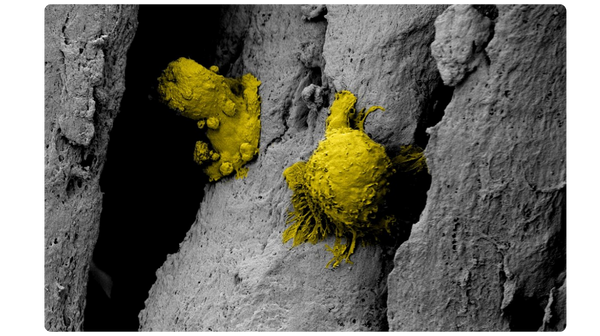

Innovative Surface Technology

The unique surface characteristics of PliaFX fibers set the standard for osseointegration.4-6 With a large surface area and well-structured demineralized cortical fibers, PliaFX provides a solid scaffold that fosters cellular viability and proliferation.4† Our proprietary processing method creates favorable porosity and microhook protrusions, improving the graft's osteoconductivity.4,10†

Scanning electron microscopy (SEM) at 3000x magnification. Images were pseudo colored in Adobe Photoshop to distinguish the cells (in yellow) from the fibers.